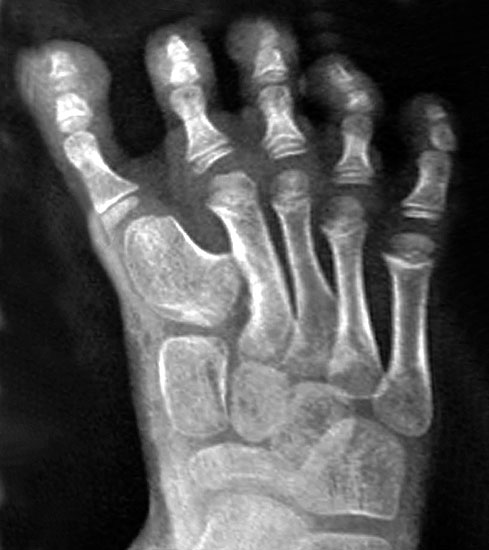

Symptomatik

Klinisches Erscheinungsbild eines Hallux varus (eigenes Bildmaterial)

Abbildung 1

Bei einer geringgradigen Ausprägung eines Hallux varus (bis ca. 10° negativer Hallux-valgus-Winkel) sind die Betroffenen selten beeinträchtigt, in der Regel bedarf es keiner Therapie. Die Korrektur durch den Druck der Zehenkappe im Schuh ist meist bereits ausreichend.

Bei zunehmender Fehlstellung klagen die Patienten über Druckbeschwerden im Schuh, insbesondere am Endglied innenseitig oder über dem IP-Gelenk der Großzehe sowie über bewegungsabhängige Schmerzen im 1. MTP-Gelenk. Häufig sind die Betroffenen auch kosmetisch unzufrieden (Janis et al., 1975).